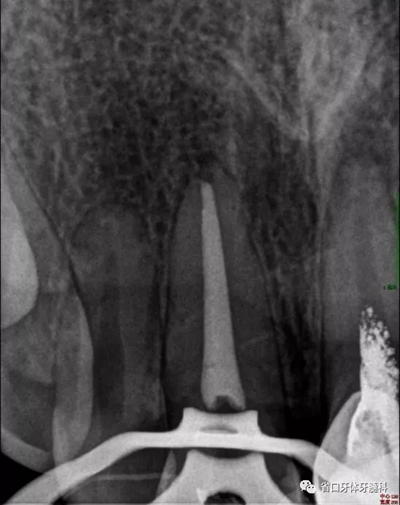

2周后復(fù)診:封藥存,患牙無(wú)不適,叩痛-,齦無(wú)紅腫。去封藥,清理根管,試主尖到位,沖洗、干燥,熱牙膠充填至釉牙骨質(zhì)界下2mm,照片顯示恰充。

圖5 根充片